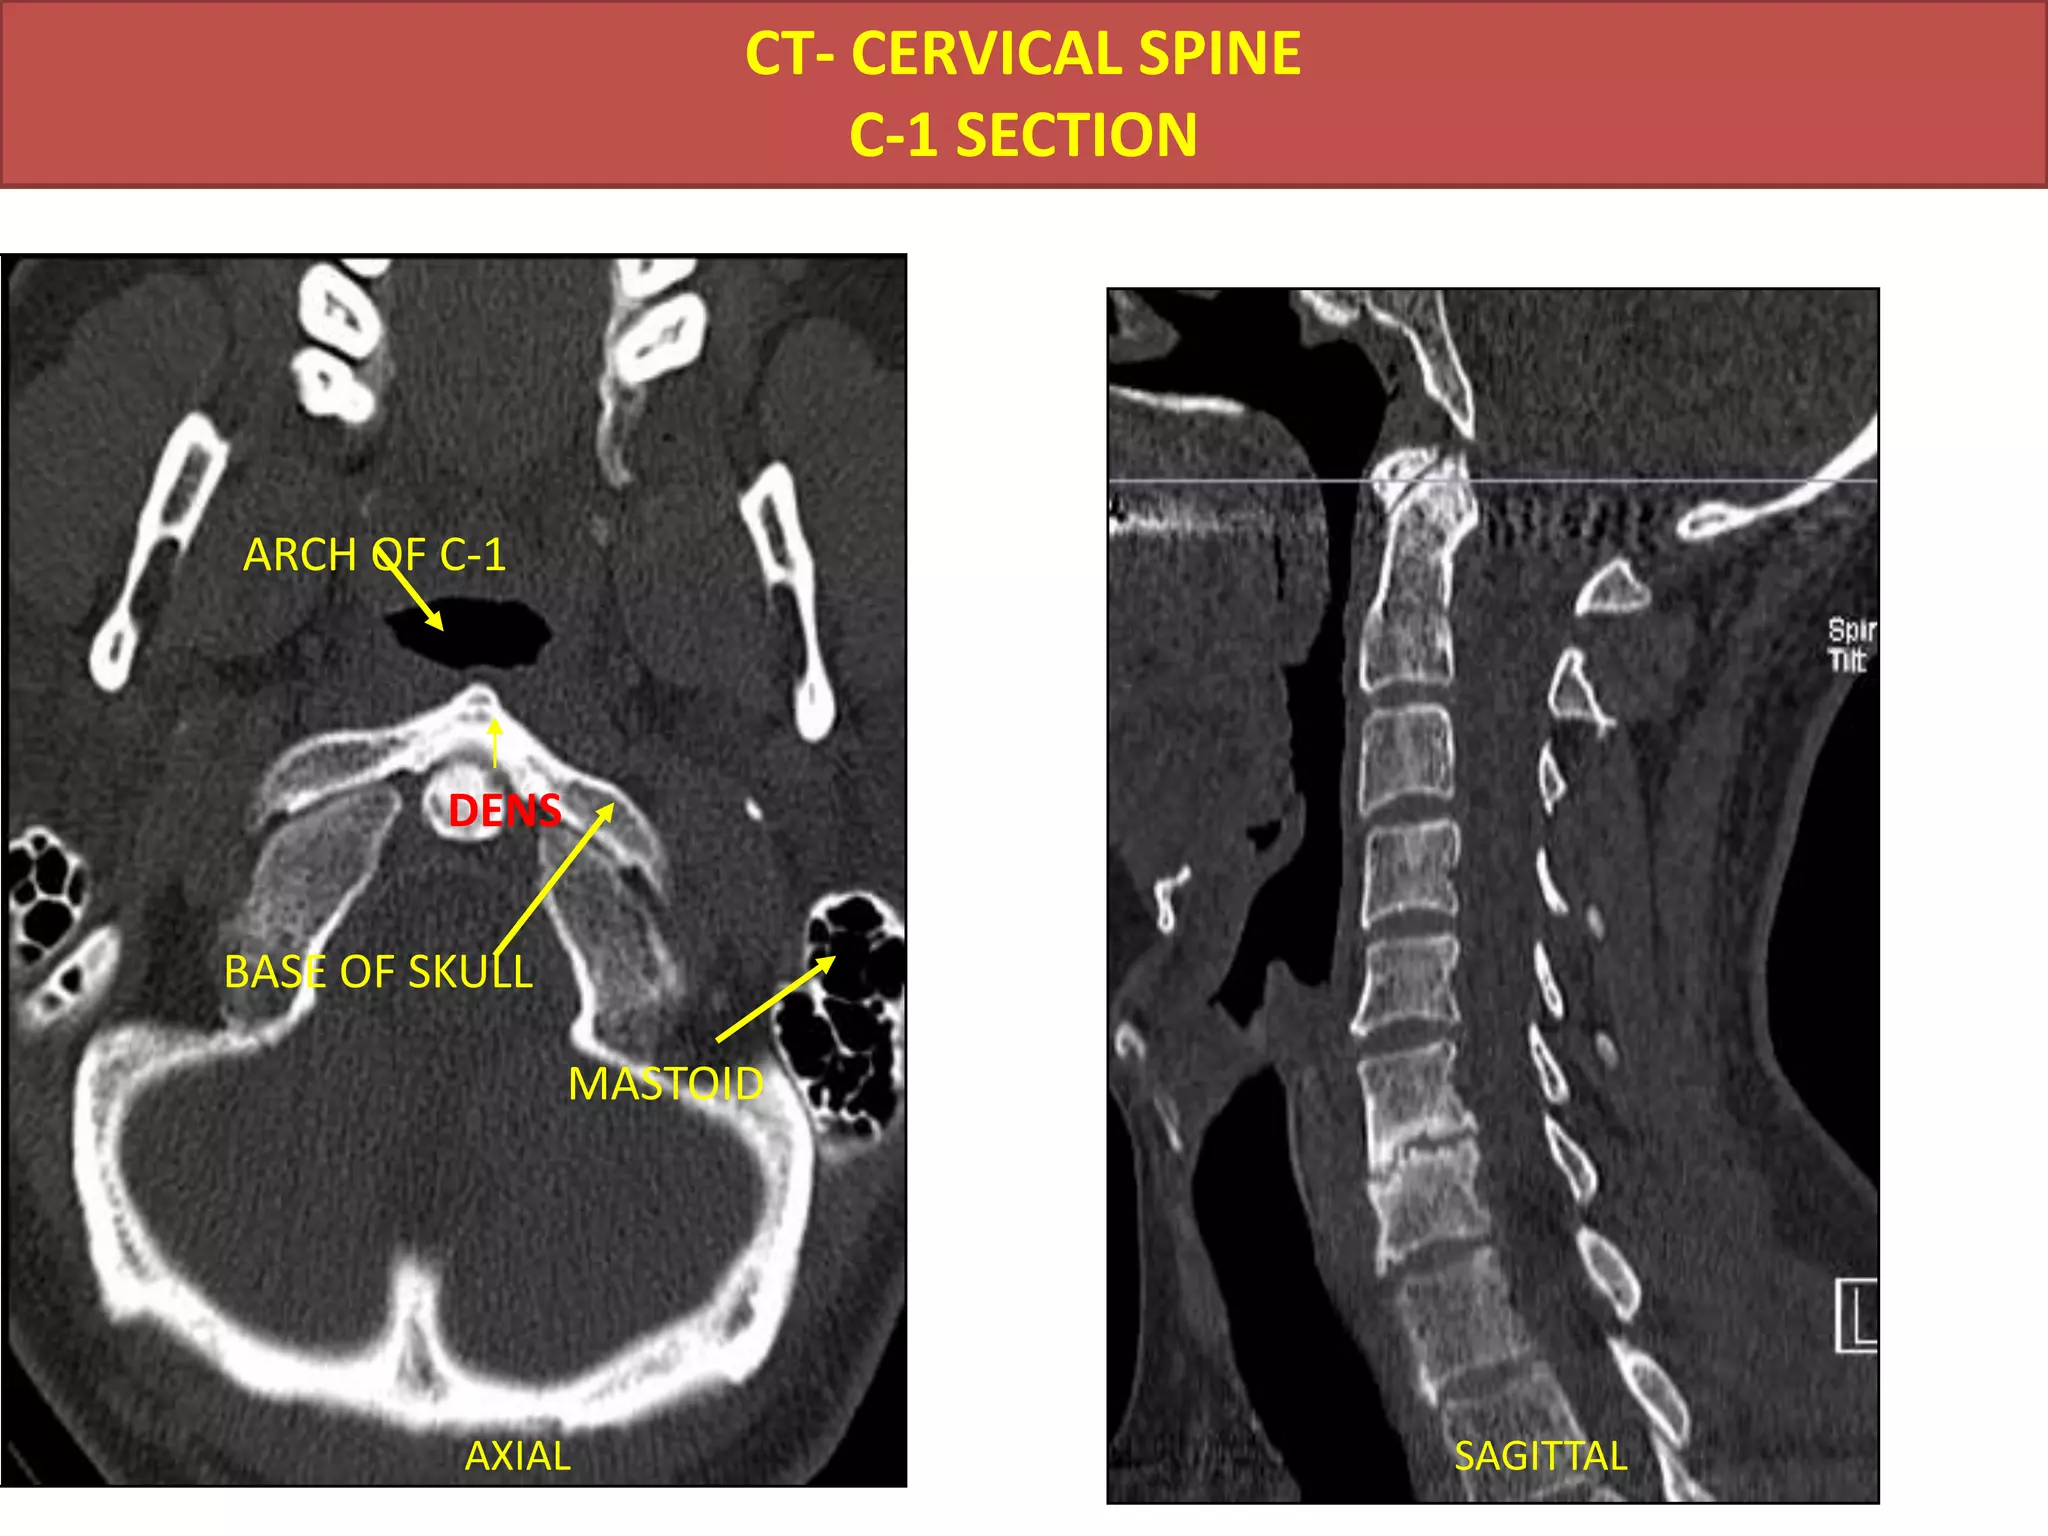

CT- CERVICAL SPINEC-1 SECTIONARCH OF C-1DENSBASE OF SKULLMASTOIDAXIALSAGITTAL

CT- CERVICAL SPINEC-1SECTIONARCH OF C-1DENSBASE OF SKULLMASTOIDAXIALSAGITTAL